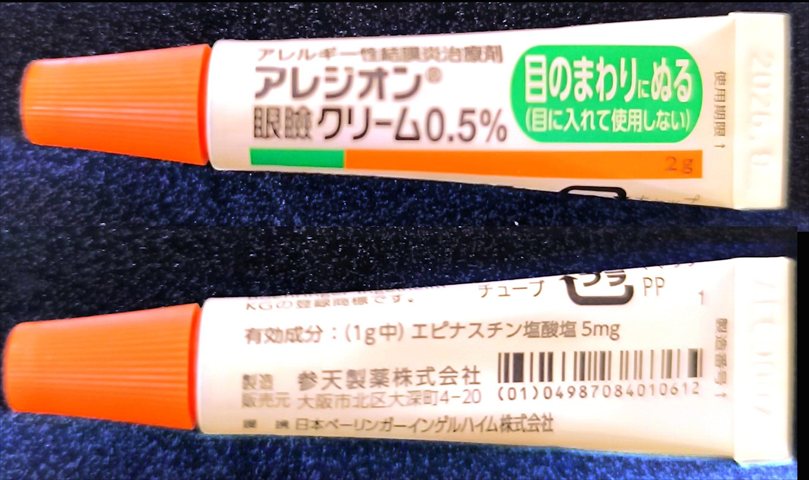

2024.3.9 点眼薬 アレジオン